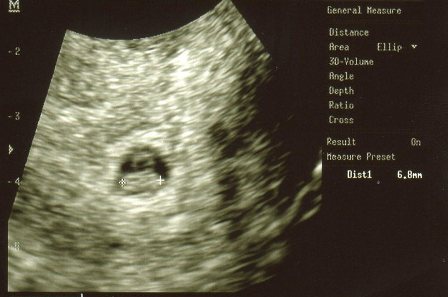

megultrahangozott és elkzdtem mondani az elözményekt( egy szülés, 3 vetélés, gyógyszerek…) nagyon figyelmes volt aztán néztük a monitort. hát sajnos az elötte napi ultrahanghoz képest a petezsák sajnos kezd belapulni, a felsö részénél kicsit beesett viszont volt benne szikhólyag- ami elözö nap nem volt- szépen látható volt. keringés még nem volt, megnézte olyan piros-kék módszerrel is amit az ultrahangon betud kapcsolni. mondta hogy az sajnos nem jelent jót ha belapul a petezsák, de még akármi lehet. azt is mondta hogy ennyi vérzés is belefér még lehet a beágyazódástól (?). hétfön a petezsák 13 mm volt most meg mivel ovális lett 12×18mm. nem kell feküdnöm, azt mondta ebben az esetben ez ugysem segit. azért dolgozni ne menjek.azt is megbeszéltük, hogy ha nem fejlödik és újra kell probálkoznunk akkor milyen elözetes kivizsgálások vannak amit az elözö doki nem csinált meg